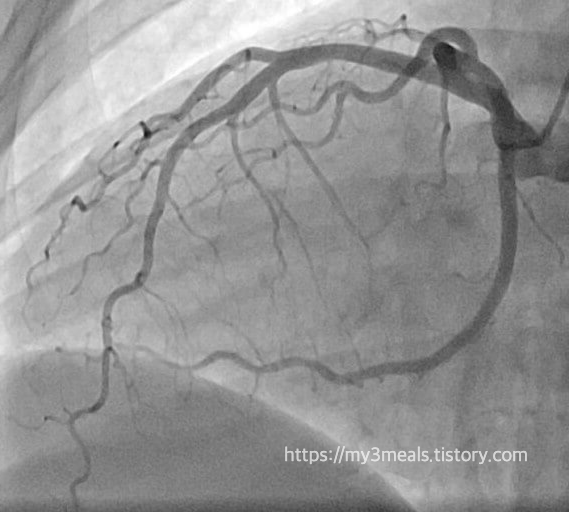

병원에 도착한 후 아버지는 곧바로 심장 조영술을 받았고, 그 결과 막힌 혈관을 확인했습니다. 의료진은 즉시 관상동맥 중재술을 시행하여 막힌 혈관에 스텐트를 삽입해 혈류를 다시 원활하게 했습니다. 이 과정은 매우 빠르게 이루어졌고, 덕분에 아버지는 심각한 합병증 없이 심근경색에서 회복하실 수 있었습니다.